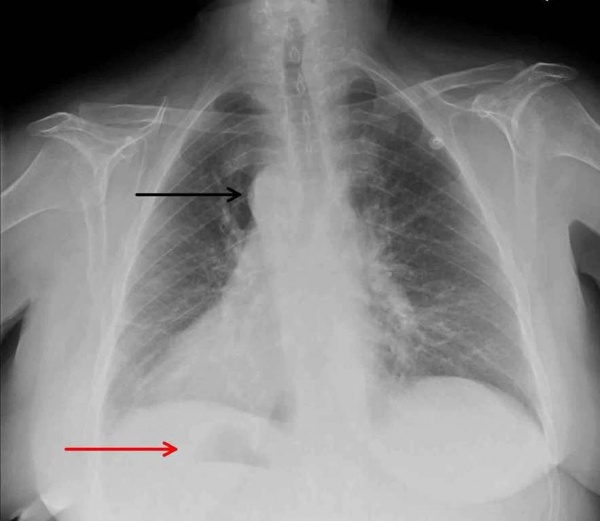

На рентгенограммах в прямой проекции на левом контуре сердца определяются две дуги: верхняя представлена часто наблюдающейся левосторонней дугой аорты и участком нисходящего отдела аорты, нижняя образована выходящим па левый контур ЛП. Дуга легочной артерии отсутствует. Правый контур сердца представляет собой сплошную выпуклую линию, простирающуюся от диафрагмы до основания сердца, которая образована вверху ПП и внизу ПЖ.

При суперэкспозиции на рентгенограммах в прямой проекции можно проследить строение трахеобропхиального дерева. В норме правый главный бронх короче, шире и отходит от трахеи под углом 25—30°, являясь как бы се продолжением. Левый главный бронх располагается более горизонтально, образуя с продольной осью трахеи угол в 45—50°. С помощью рентгенологического исследования исключают экстракардиальные факторы, которые могли бы привести к правостороннему положеиию сердца. При контрастном исследовании желудочно-кишечного тракта устанавливают его нормальное строение и расположение. Приблизительно в 7—10% случаев можно отметить абдоминальную гетеротаксию. С помощью внутривенной холецистографии определяют нормальную форму и локализацию желчного пузыря. При радиоизотопном сканировании печени и селезенки обнаруживается их обычная позиция.

Определенную ценность представляют также сведения о строении трахеобронхиального дерева. Это основано на наблюдениях, из которых следует, что анатомически правый бронх обычно бывает на стороне локализации правого предсердия (ПП), а анатомически левый бронх — на стороне ЛП (Van Mierop et al., 1970). Такие данные можно получить при анализе рентгенограмм, сделанных при суперэкспозиции в переднезадней проекции.

Дуга аорты и воздушпый пузырь желудка, видимые при рентгенологическом исследовании, при известных допущениях также могут служить косвенными показателями положения предсердий, но лишь в тех случаях, когда они расположены с одной и той же стороны (Elliott, Schiebler, 1968). Например, левосторонняя локализация дуги аорты и газового пузыря желудка свидетельствует о наличии правосформированного сердца, а правосторонняя—о левосформированном сердце.

- Рентгенография ОГК. На рентгенограмме визуализируется смещение сердечной тени вправо, при комбинированных аномалиях изменяются контуры магистральных сосудов. Чтобы подтвердить транспозицию проводится рентгенография органов брюшной полости.